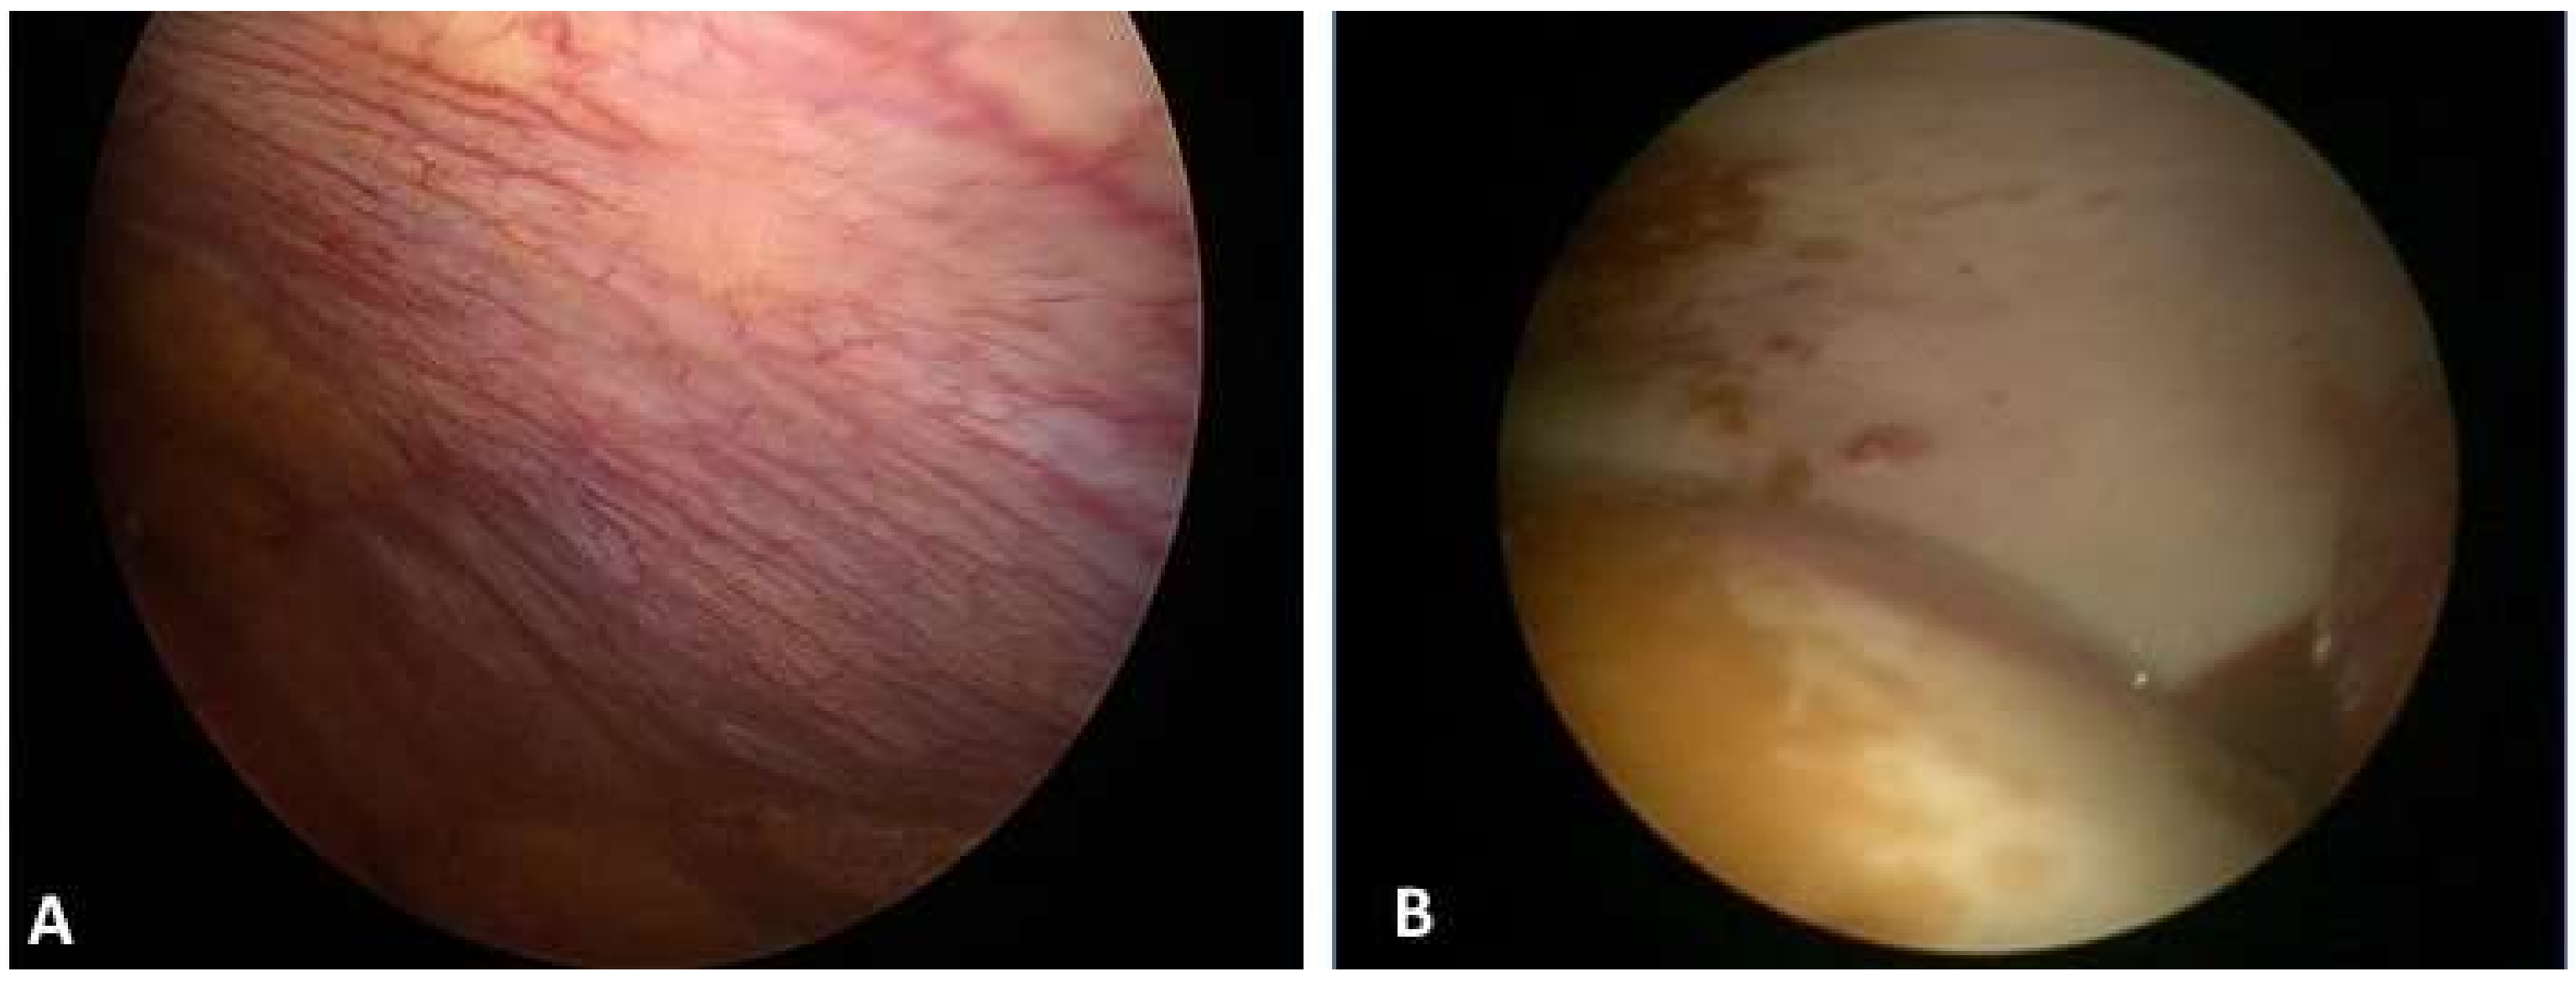

2. Case Presentation